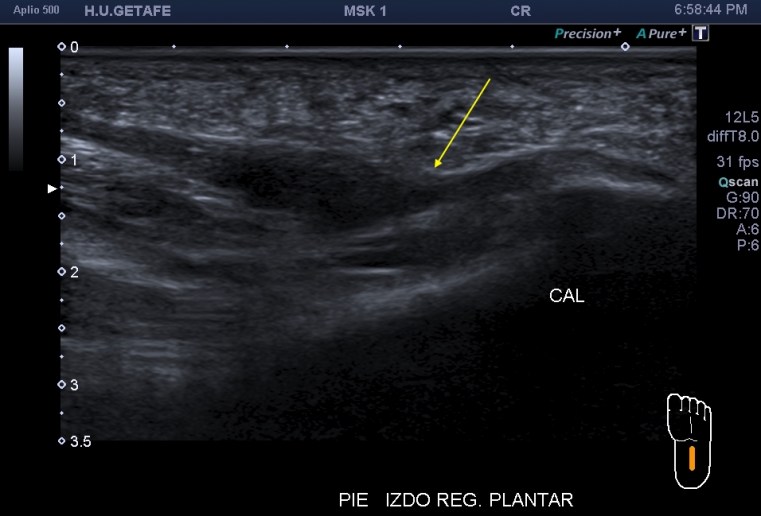

Me llama poderosamente la atención, lo recuerdo perfectamente, la normalidad del recto anterior, pero después de buscar un poco observo como el vasto intermedio si está «distinto», algo heterogéneo, voy a comparar con el lado contralateral y bingo¡ el vasto intermedio, que es de esa musculatura «que nunca tiene nada», modo «ironía on», te sorprende…y la ecografía muscular es como el océano, nunca puedes confiarte…

Mira las imágenes y tu misma te darás cuenta:

La zona que presenta mayor abombamiento y empastamiento (cara lateral del muslo izquierdo), se visualiza aumento del grosor del fascículo muscular correspondiente con el vasto intermedio, sin poder evidenciarse la presencia de lesiones definidas. El diagnóstico es un aumento difuso e inespecífico del Vasto Intermedio, sin masas ni roturas. A valorar con RMN.